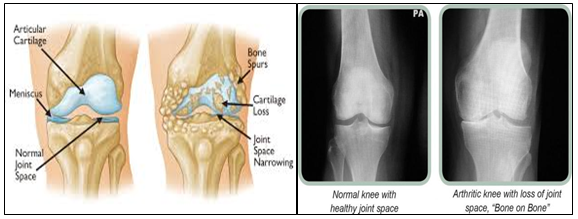

Osteoarthritis is the most common type of arthritis affecting the knee. It starts as wear and tear of the soft cartilage in and around the knee. The degenerative changes can, if not managed, continue and end up in pain and restricted movements of the joint. It can affect people of all ages but mostly affects after the age of 50. The cushion like cartilage, present between the bones,wears out partially or completely resulting in this condition.

Pain, stiffness, crackling sound from the joints are the major symptoms. Damage from mechanical stress like over activity, obesity, loss of strength of muscles supporting the joint, wrong movements etc are the few major reasons for the wear and tear to start and lead to degeneration. Changes in hormone levels in females also contribute to osteoarthritis